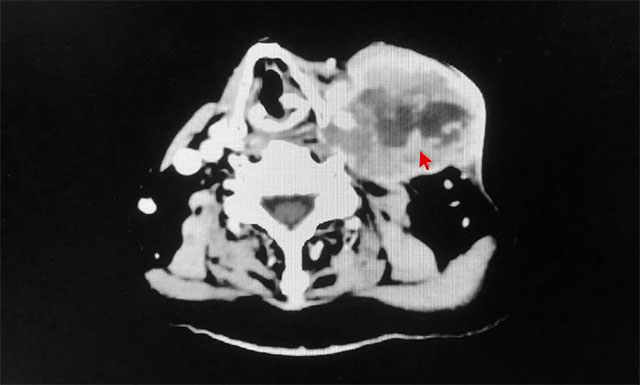

近日,上海藍十字腦科醫(yī)院腫瘤科(放療)收治了一位喉癌淋巴轉移患者。年過七旬的患者李某(化名),因“喉癌術后8年,左側頸部包塊2月余”入院。該患者于2013年在福建某大醫(yī)院確診喉部占位,伴喉白斑,并行喉部腫瘤微創(chuàng)切除術,術后病理顯示:原位癌。其后,患者喉部腫瘤兩次復發(fā),行手術切除治療。去年10月,患者發(fā)現(xiàn)左側頸部有淋巴結腫大,進行性增大。于今年2月行左頸部淋巴結轉移灶穿刺活檢,病理示:鱗狀細胞癌,中度分化。

▲ 患者左側頸部淋巴結轉移,腫瘤體積較大

經親友推薦,患者慕名來到上海藍十字腦科醫(yī)院尋求進一步治療。經詳細檢查,該患者喉癌病史數年,診斷明確,既往已行三次手術,目前左側頸部淋巴結轉移,腫瘤體積較大,且腫瘤包繞血管,無再次手術適應癥。醫(yī)院腫瘤科(放療)主任王曉東與其團隊就患者病情予以詳細討論及評估,結合患者入院后各項常規(guī)檢查結果,排除放射治療禁忌癥,明確告知患者及家屬目前病情情況、放射過程中各種臨床并發(fā)癥及副作用,以及患者整體預后情況,予以簽字同意后,王曉東團隊仔細勾畫患者腫瘤靶區(qū)及臨床靶區(qū),物理師精心設計放射治療方案,為患者開展了加速器放射治療。